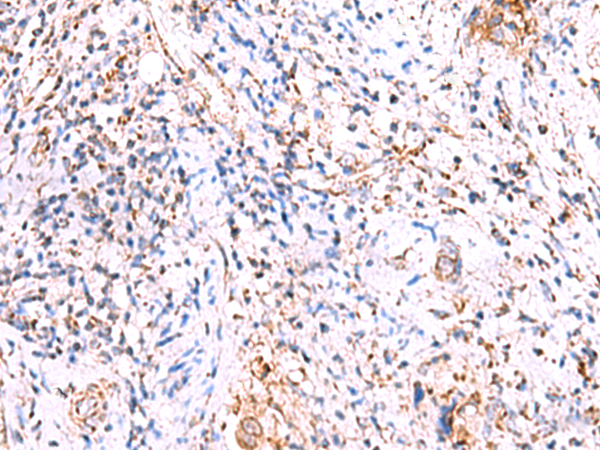

分类: 科研抗体货号: P13552别名:应用: IHC反应种属: Human